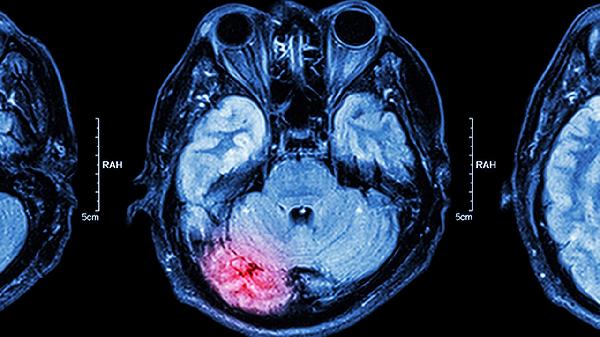

脑得生丸有活血化瘀的功效,也可以通经活络,促进因为瘀血阻络引起的眩晕、中风等症状消失,也可以用于脑动脉硬化、缺血性脑中风及脑出血后遗症的辅助治疗。如果您存在肢体不用、言语不利等症状时,也可以使用这种中成药物调理。

需要注意的是由于脑得生丸为活血化瘀的制剂,因此孕妇和脑出血急性期的患者一般忌用。若患者在服用脑得生丸的同时还需服用其他药物,需提前咨询医生,以免药物之间发生相互作用,对患者机体健康造成影响。